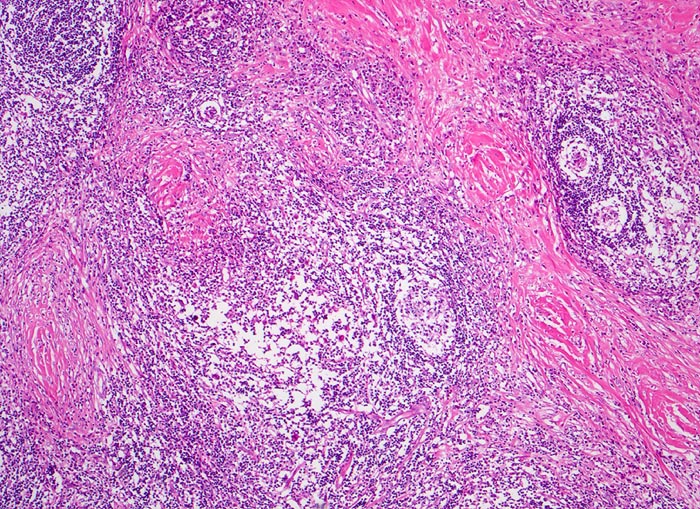

Histologisch charakteristisch für diesen Subtyp sind Sklerose, noduläres Wachstumsmuster und Lakunarzellen. Bei der nodulären Sklerose können Grad I und Grad II (15-25%) Lymphome unterschieden werden; unter modernen Therapiekonzepten allerdings ohne prognostische Bedeutung

Morphologische Merkmale:

• Zerstörung der Lymphknotenarchitektur.

• Von breiten Bindegewebssträngen abgegrenzte Knoten.

• Die Knoten bestehen vorwiegend aus einem Mischzellinfiltrat reaktiver Zellen: Lymphozyten, Histiozyten, eosinophile Granulozyten und Plasmazellen.

• Reed-Sternbergzelle mit spiegelbildlich angeordneten Kernen mit sehr grossen eosinophilen Nukleolen.

• Einkernige Hodgkinzelle mit prominentem Nukleolus umgeben von einem Retraktionsartefakt (Lakunarzelle).